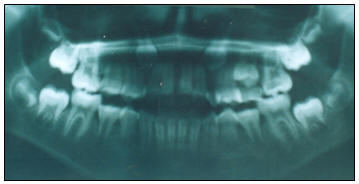

4.-

Radiografías.- En la radiografía panorámica, debemos señalar

la presencia de los cuatros terceros molares en evolución

intraósea, continúa el recambio de piezas primarias, para

nombrar la dentadura permanente se usará el sistema FDI.

(Fig. 3)

Fig. 3.- En la que

podemos observar a los cuatro terceros molares en

evolución intraósea, la mordida abierta se nota de

premolar a premolar |